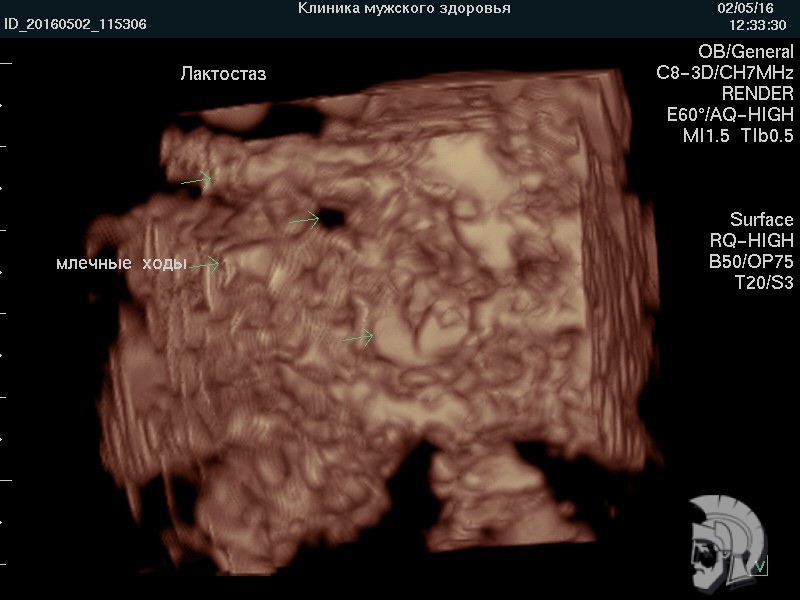

Фото лактостаза в режиме 3D. Тот же случай.

Расширенные и заполненные молоком млечные ходы указаны стрелками.

Мужчина ВОВРЕМЯ привел жену. Грудь сохранили БЕЗ ОПЕРАЦИИ |